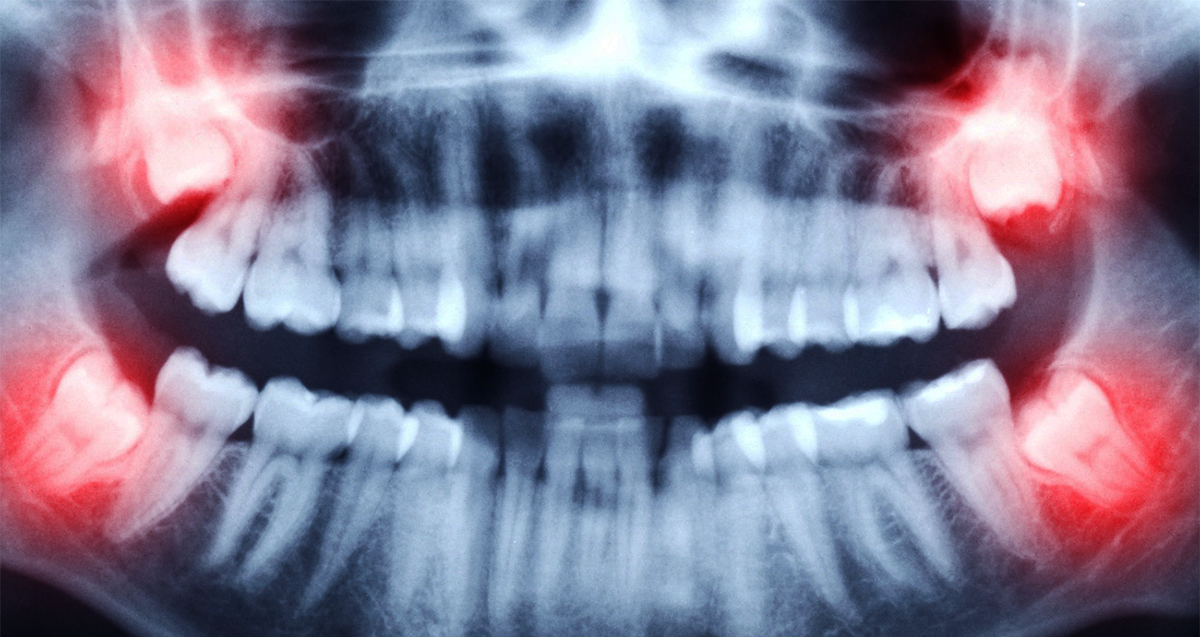

Зубы мудрости. В процессе эволюции челюсть человека стала меньше, и эти зубы стали буквально "не влезать" в рот человека. Их в большинстве случаев удаляют, иначе они деформируют остальные зубы. В общем хочется, чтобы они поскорее исчезли.